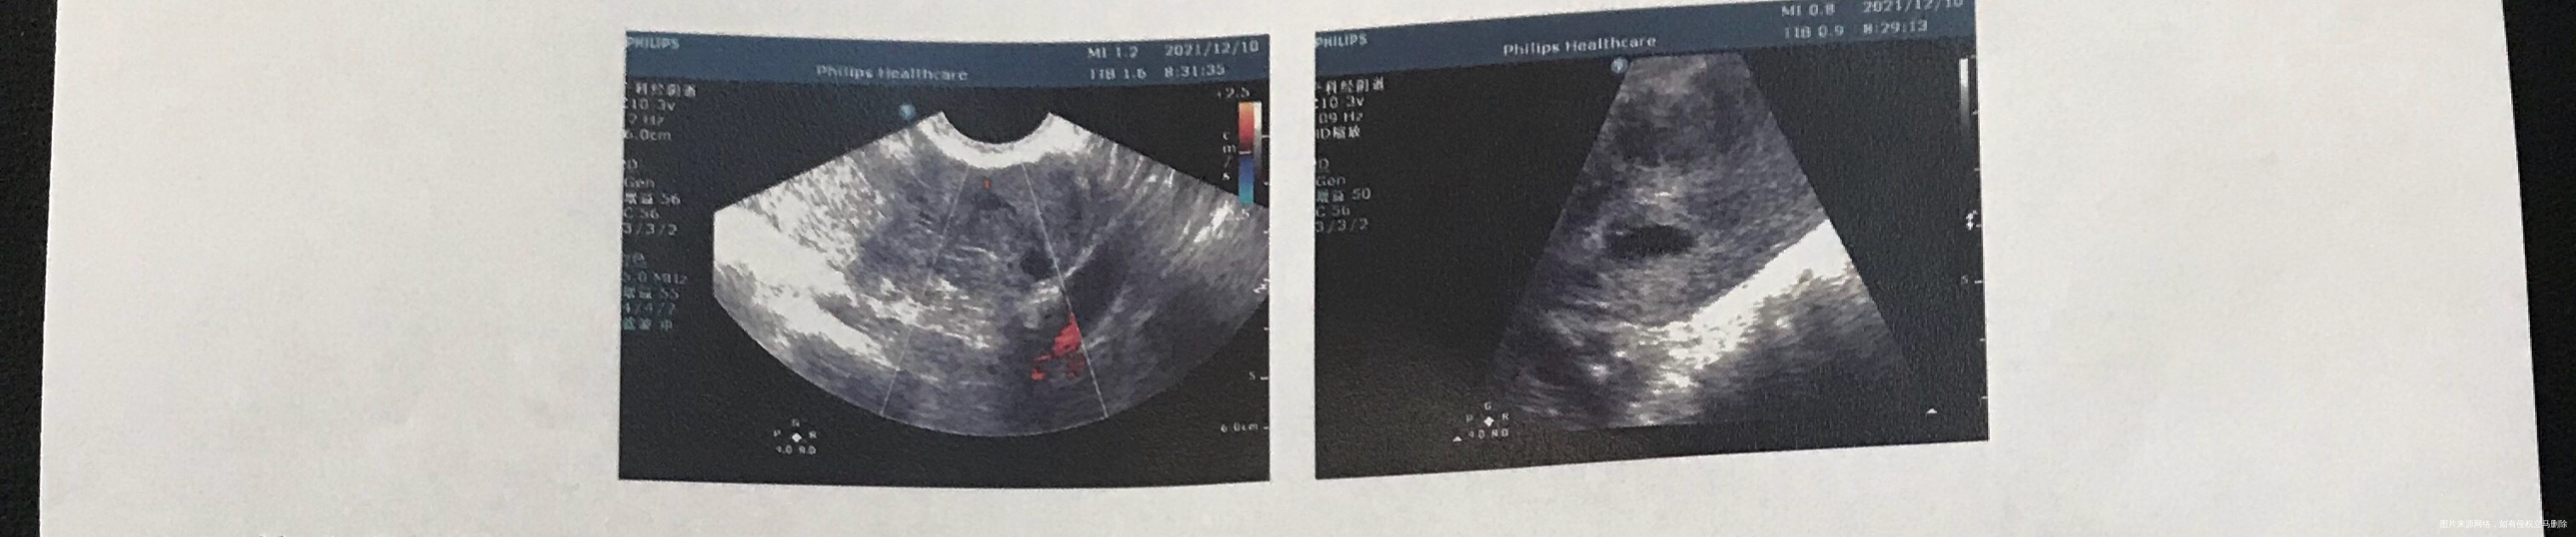

您好大夫,11月17日试管移植2个胚胎,12月10日一超显示宫内偏右宫角一个孕囊,13✖️7mm,内有卵黄囊,左边提示有个偏实性包块,11✖️11mm,内有不均质略低回声,cdfi周围可见少许点状血流信号,报告写的可能是增生输卵管?(之前造影通而不畅伴粘连),比较担心,另一个有没有宫外的可能?hcg翻倍正常,目前已经大于1万

目前B超看到了偏宫角有一个孕囊,左侧有一个类似孕囊的回声,所以现在就考虑有宫外孕的问题。不管是宫角的这个还是在左侧的这个,都还需要继续复查明确诊断。

严密观察随诊,不能排除左侧宫外孕和右侧宫角妊娠的风险。如果突然腹痛及时随诊。